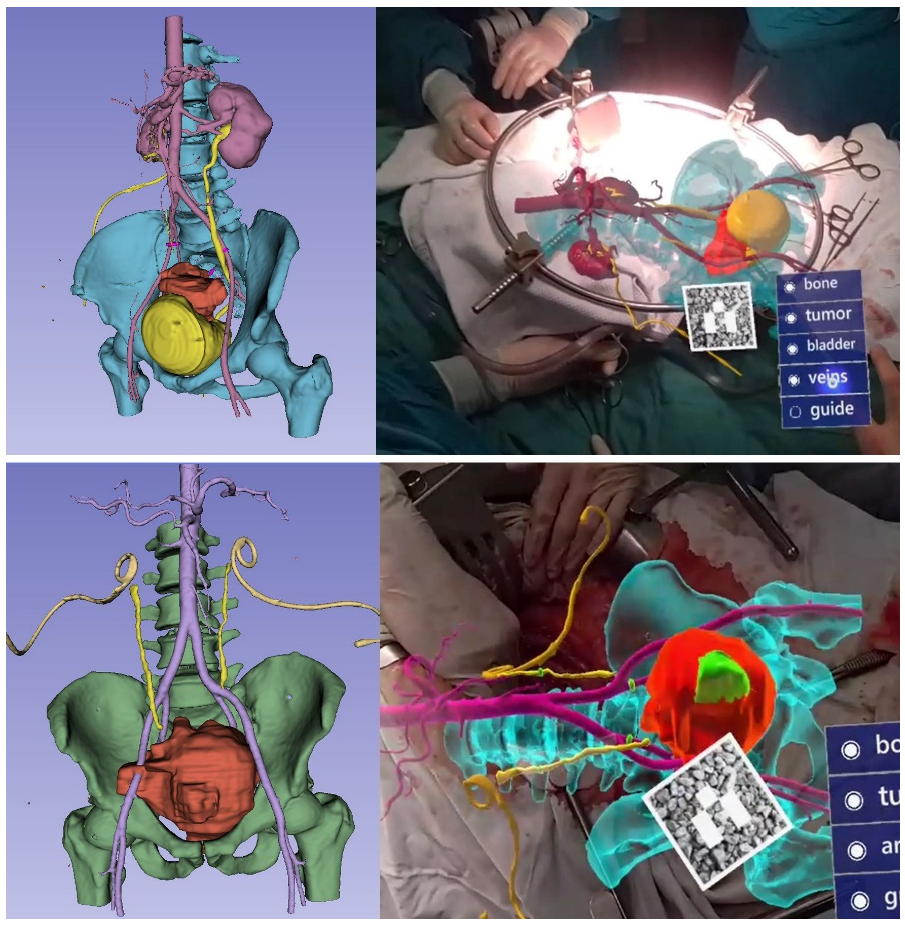

3.1. Clinical Experience in Cases with Invasive Markers

3.2. Clinical Experience in Cases with Noninvasive (Skinbased) Markers

3.3. Hologram Positioning Accuracy

- Gestures control menu